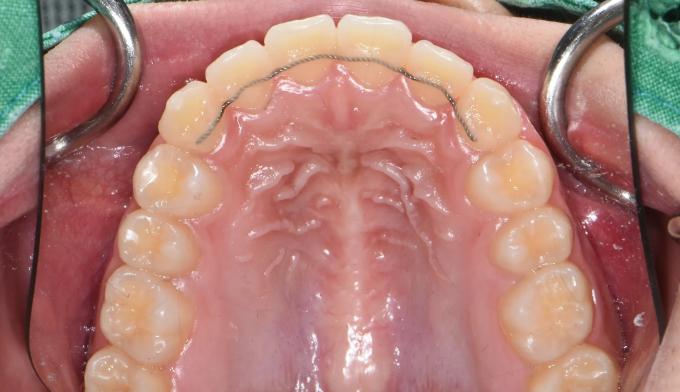

덧니

심하지 않은 덧니의 경우에는 교정기간이 비교적 짧습니다.

확장장치와 같은 부가적인 교정장치가 필요없기 때문에 교정기간이 단축될 수 있습니다.

그리고 이 모든것은 아직 성장중인 학생이기에 가능한 일입니다.

총 교정기간은 13개월입니다.